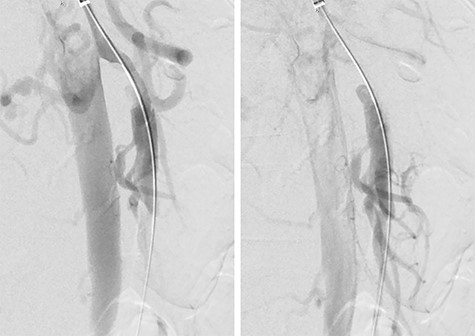

A 52-year-old woman presented to the emergency department with 3 days of diffuse abdominal pain that started during a dance class. The pain had a sudden onset with radiation to her back and did not worsen with meals. She had mild associated nausea and bloating but no other symptoms including emesis, hematochezia, melena or diarrhea. Her medical history was notable for former smoking history (10 pack-years, quit 5 weeks prior to presentation), but she was otherwise healthy and was taking no medications. Her surgical history consisted of laparoscopic appendectomy and diagnostic laparoscopy for endometriosis, both of which occurred more than a decade prior to presentation. She was hemodynamically stable with systolic blood pressure ranging from 100 to 120 s mmHg, and her exam was notable for mild diffuse abdominal tenderness without evidence of peritonitis. Her complete blood count and basic metabolic panel were within normal limits, and a venous blood gas demonstrated no evidence of lactic acidosis. A computed tomography (CT) angiogram of the abdomen and pelvis demonstrated a 5–6 cm length proximal SMA dissection with high-grade stenosis of the true lumen as well as a short-segment right external iliac artery dissection with mild narrowing of the true lumen (Fig. 1). There was no radiographic evidence of bowel ischemia.

CT angiogram of the SMA dissection demonstrating the Left: false lumen supplying the middle colic artery with Right: the narrowed true lumen supplying the other SMA branches.